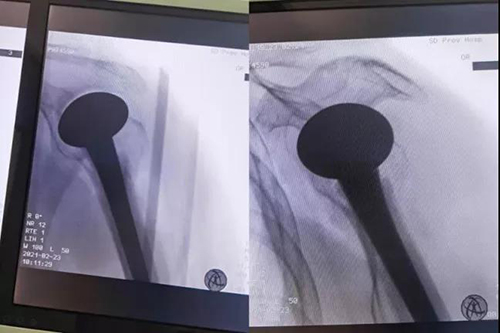

术中透视及术后X线